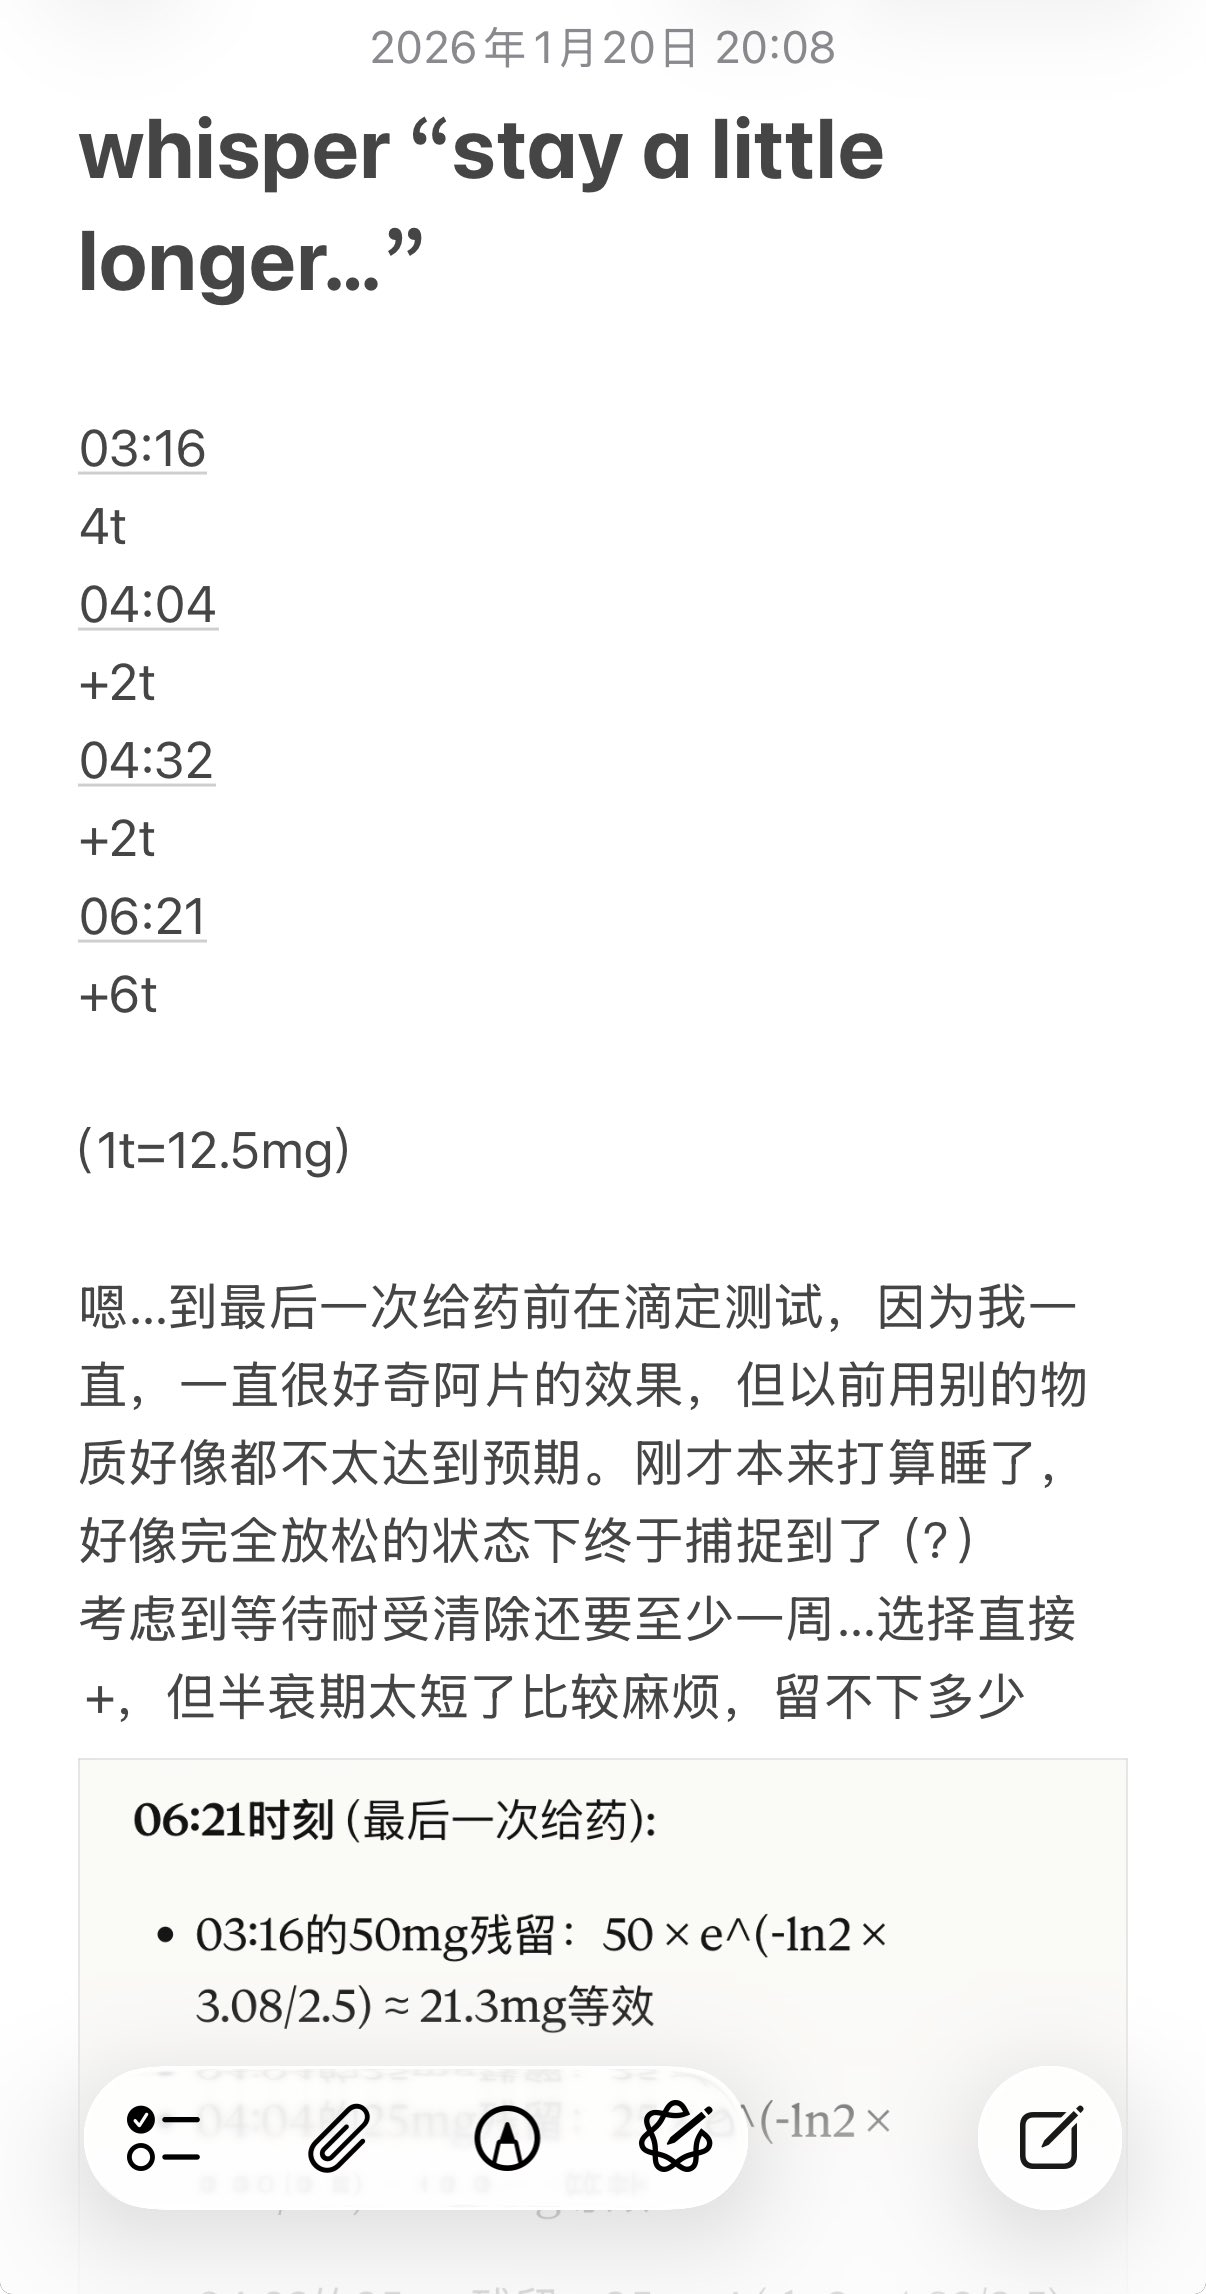

2026-01-22 19:09:20 UTC

化学带来的幸福感不需要外在环境的配合,它直接作用于你感知幸福的能力本身…

今天起来特别晕,完全不知道是怎么回事,以为是昨天测试物质的副作用我在想这么恐怖,然后怀疑今天是不是丁螺环酮吃了两次,直到我去看用药记录。。

好家伙唑吡坦又骗我吃药了还顺带上了个失忆状态,这下子知道是谁干的了。吃auv之后dxm清除得特别慢...让我感觉要从此告别了的程度,加上我基因检测本来cyp2d6就是中速代谢,这个尾巴就被拖的特别长

想起来昨天是因为完全看不懂字了什么都干不了才睡觉的,还好没去骚扰别人()

炽烈已极 @AnIncandescence@oct424242 实际上我判断这是dxm干的,真相大白了

炽烈已极 @AnIncandescence醒了躺在床上的时候想着怎么还有内幻呢,像是在拉摇杆操纵游戏里的小人,以一个俯瞰的视角(经典)

炽烈已极 @AnIncandescence迷迷糊糊的平白无故很开心,想着原来冬天睡觉这么舒服的吗在被子里蛄蛹()后来真相大白是刷出欣快tag了,robo就是比较容易出